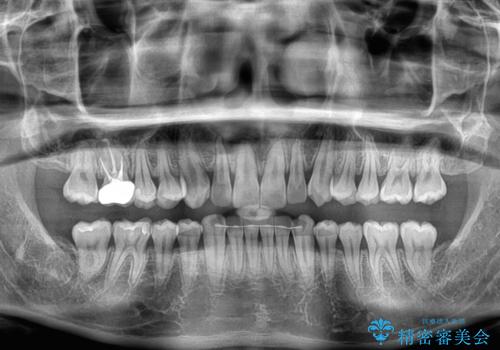

- 前歯のデコボコと突出感を気にして来院された患者様です。

極力目立たない装置を希望とのことで、インビザラインを用いて非抜歯で矯正治療を行うこととしました。

事前に親知らず4本を抜歯し、多少歯列を後方に移動できるように準備をした上で、なるべく歯と歯の間を削ることなくデコボコを解消できるように計画しました。

途中、以前大きなむし歯で処置をした歯が痛み出し、根管治療が必要となったため、根管治療とオールセラミッククラウンによる補綴治療を行い、その後にインビザラインによる仕上げの歯列移動を行い、無事に治療を終えることができました。